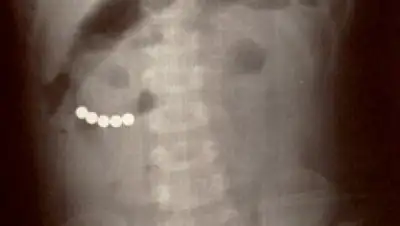

Пятилетний ребенок, проглотивший 38 магнитных шариков, идет на поправку в Алматы, рассказал Sputnik Казахстан заведующий приемным покоем центра детской неотложной медицинской помощи Ерлан Мендигалиев.

"Ребенок сам дышит, состояние соответствует тяжести перенесенной операции. Разговаривает, в сознании. Конечно, идет на поправку. Если все будет хорошо, то еще 7-10 дней пробудет в больнице. Сейчас ребенок в реанимации, переводить в обычную палату планируем через день-два", — прокомментировал Мендигалиев.